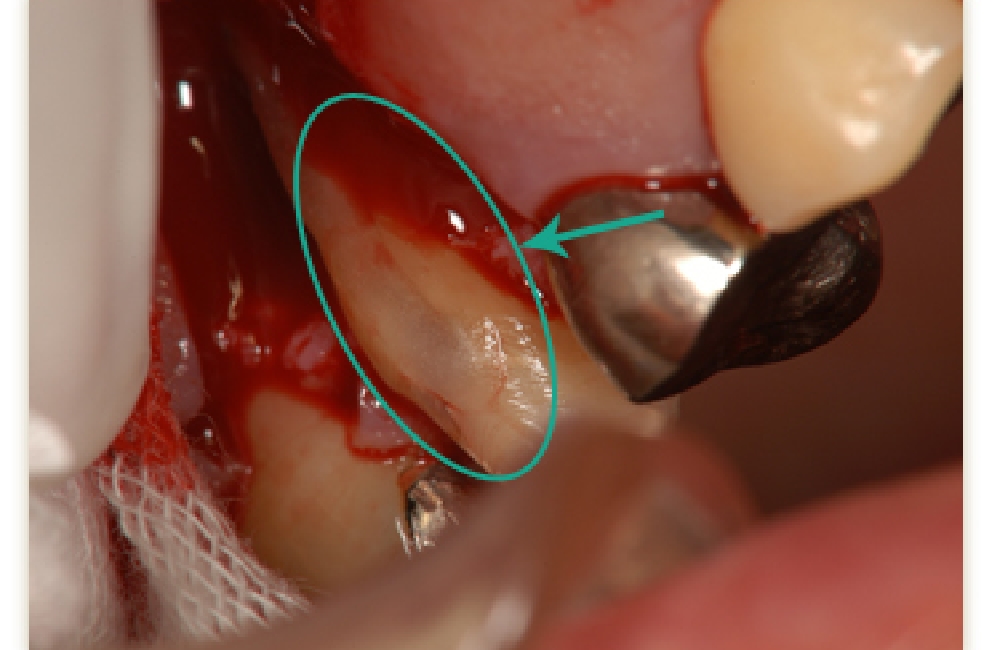

口腔内接着法

破折部分が比較的小さい場合に行う方法です。

破折部を洗浄し、新鮮な歯質を露出させたうえで、生体親和性の高い接着剤を用いて封鎖します。